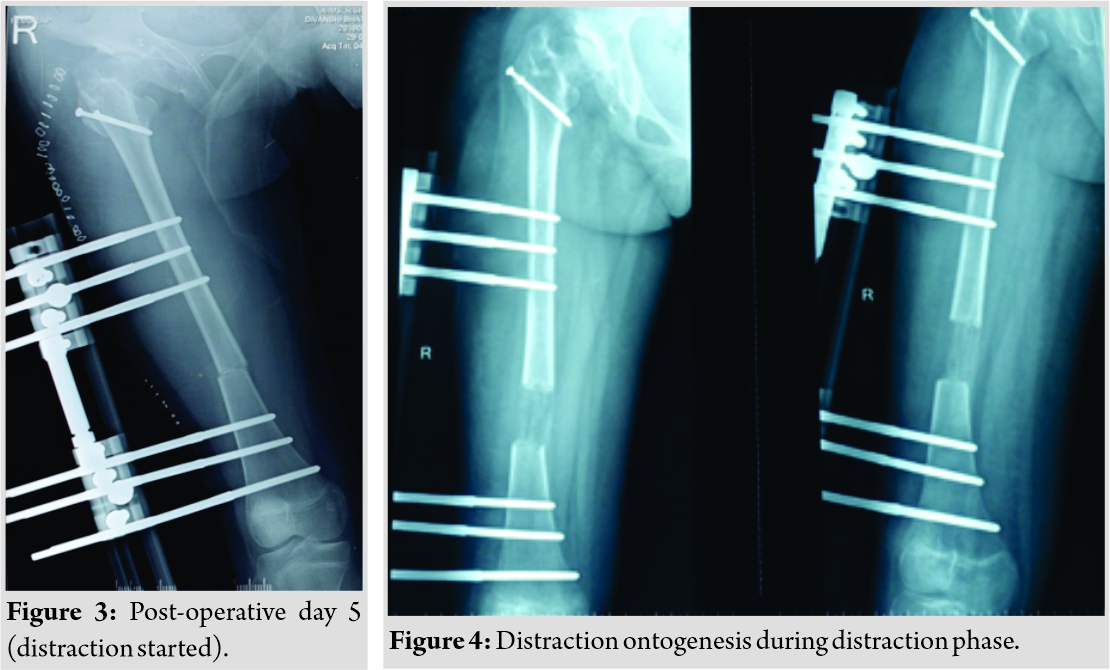

A 13-year-old female patient presented with complaints of painless limp in the right lower limb. The patient had a significant history of septic arthritis of the right hip joint which was managed conservatively in the past. On examination, it was found that the patient had a stable (negative telescopic test) and mobile hip with moderate restriction of abduction (20°). There was no fixed deformity. There was 7 cm of true femoral shortening. The child walked with a Trendelenburg gait with an added component of shortening which was partially compensated by ankle equinus. Radiological investigations revealed severe coxa vara with the steep acetabular inclination and was classified as Choi’s Type 2 septic hip sequel. Based on this workup, it was found that the child was having abductor lurch and femoral shortening, and both needed to be addressed. The patient was put on a lateral position in the operation theater and proximal femur was opened by a posterolateral approach. The hip abductors were carefully identified at their insertion on the greater trochanter (GT) and also the vastus lateralis distally. Piriformis tendon was also carefully identified. A 2 cm thickness of GT with attached abductors proximally and vastus lateralis distally was elevated with an oscillating saw (Fig. 2).  Care was taken to preserve the piriformis attachment on to main femoral fragment. With the help of patella holding clamp, the GT fragment was held and shifted to 2 cm distally and fixed with two 4 mm cannulated cancellous screws. The wound was closed over the suction drain and the patient was then planned for monorail external fixator in the supine position. Gradual distraction was started from the 5th post-operative day (Fig. 3).

Care was taken to preserve the piriformis attachment on to main femoral fragment. With the help of patella holding clamp, the GT fragment was held and shifted to 2 cm distally and fixed with two 4 mm cannulated cancellous screws. The wound was closed over the suction drain and the patient was then planned for monorail external fixator in the supine position. Gradual distraction was started from the 5th post-operative day (Fig. 3).  Careful follow-up evaluation was done and distraction was stopped once limb length equalization was achieved (Fig. 4-6). The fixator was removed after 112 days. The patient had no complication postoperatively except mild pain during early phases of distraction which was managed with high-dose analgesics and knee stiffness in the later part of the distraction. She achieved a complete range of motion of knee with extensive physiotherapy and quadriceps strengthening exercises. At final follow-up of 6 months, the patient had no equinus at the ankle with improvement in hip abduction with minimal abductor lurch.